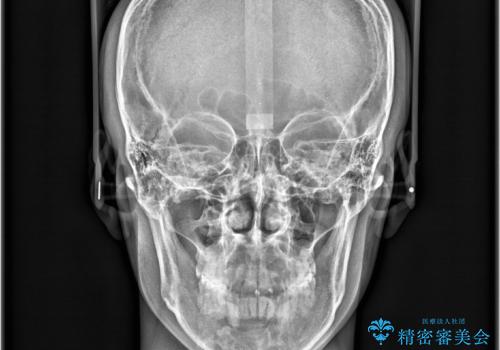

- 咬み合わせの不調和と歯並びのデコボコを主訴にご来院された患者様です。

精密矯正検査の結果、歯を抜かずに非抜歯でワイヤー矯正で治療を行う方針としました。

叢生(歯のデコボコ)の量が多く、加えてディープバイト(過蓋咬合)や重度の捻転も認められたため、リンガルアーチやマイクロインプラントなどの補助装置を併用し、治療を進めました。